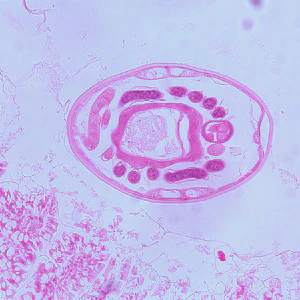

Hookworm eggs.

Microscopic identification of eggs in the stool is the most common method for diagnosing hookworm infection. The recommended procedure is as follows:

- Examine a wet mount of the sediment.

Where concentration procedures are not available, a direct wet mount examination of the specimen is adequate for detecting moderate to heavy infections. For quantitative assessments of infection, various methods such as the Kato-Katz, FLOTAC and Mini-FLOTAC may be used.